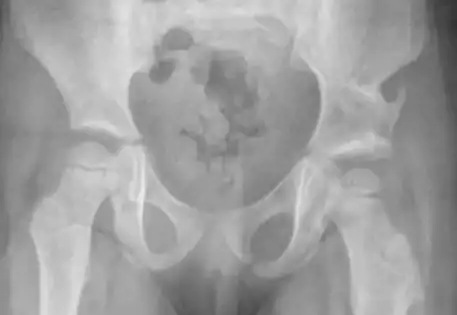

Clinical case B : 2 year old boy presenting with dislocation of both hips

According to the International Hip Dysplasia Institute, one in five hundred children is born with a dislocated hip. Although some will be diagnosed at birth, many will evade clinical detection and present when the child is walking age and a painless limp or asymmetry in the legs is noted. In children older than six months, an X-ray is a better investigation than an ultrasound to diagnose hip dysplasia.